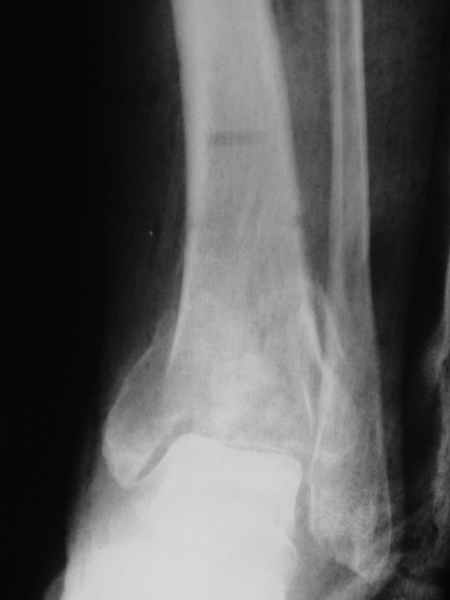

The situation at the ankle is now like a stiff non-union.

The cartilages destroyed by the infection, there is only bone proximal (tibia) and bone distal (talus)

Putting this under distraction would very likely lead to a consolidation of the 'gap' created with bone.

This supports Alex's proposal for closed distraction.

In one of my cases, with a non-union of the distal tibia, and a stiff ankle with equinus, as part of the treatment, I distracted the ankle, with the hope of 'loosening' up the ankle, and correcting the equinus,

To my surprise, this distracted area made bone, effectively converting a painful, stiff, fibrous ankle into a solidly fused, painless ankle.

Pic attached - the transarticular K wire/steinman pin was put in by the previous surgeon, to stabilise what was apparently a very unstable

ankle.

I don't have his pre-distraction pics, but take my word for it, the ankle space was seen, though hazy, and the patient had pain on attempted movts of the ankle.

Mangal Parihar